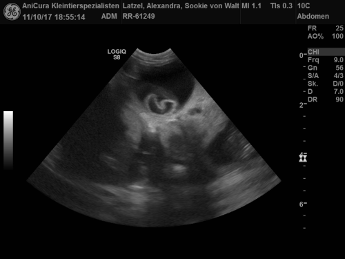

| 11.10.2017 |

| Sookie ist werdende Mami! Im Ultraschall haben wir vier Welpis gesehen! Hier die Bilder!!! |